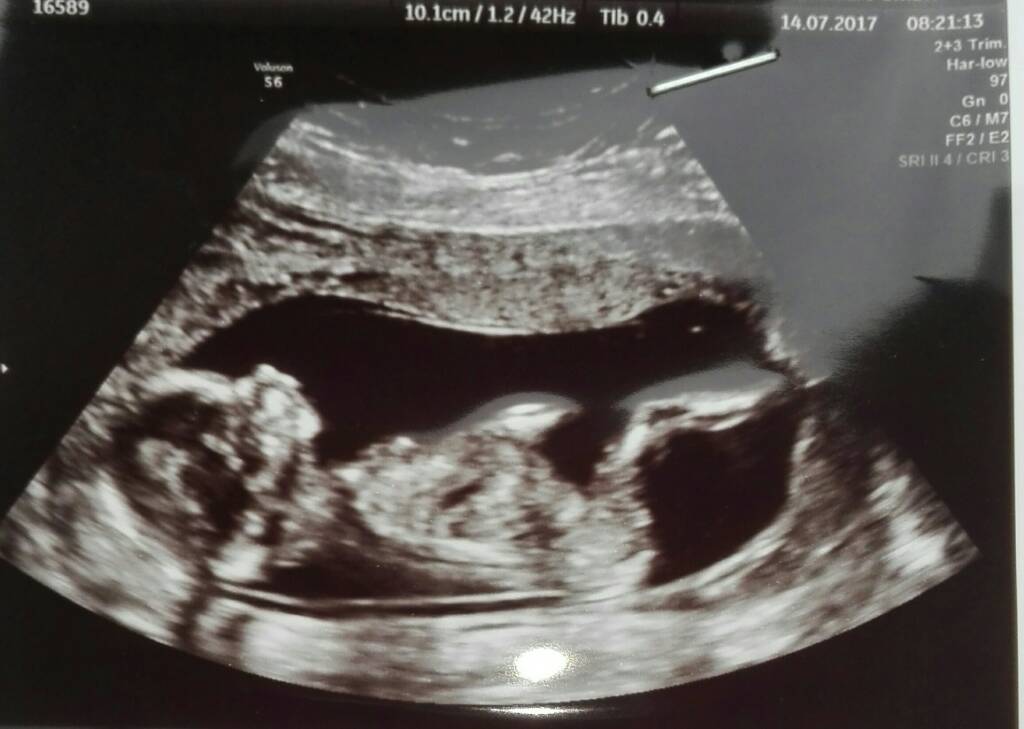

Achaaa oki, to sorkiNiee, to są parametry maszyny usg bo na kazdej tak mam. Rozmiar dziecka to CRL

Cudna [emoji7]Zosia jest Zosią nic Jej nie wyrosłoma się kwitnąco. Tylko z tego wszystkiego nie wiem ile mierzy. Krwiak się wchłonąl. Plamienie jest od odklejajacej sie owodni i pewnie się utrzyma do 16tc, ale w takim miejscu, że nie zagraża Małej a ja najlepiej leżeć mam